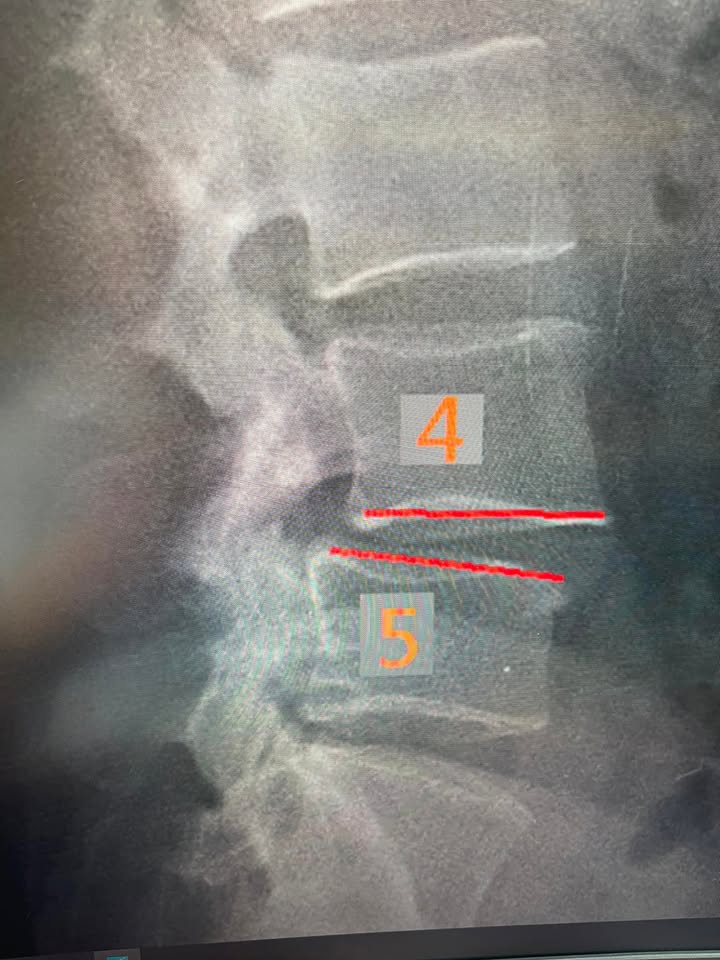

「原本困擾好幾年的腰部不適,原來是腰椎退化擠壓與滑脱導致,陸續做了一陣子的復健也不見好轉..偶然在FB上看到徐醫師的針刀治療成功案例,不禁燃起一絲希望,預約了看診的第一天,徐醫師就仔細講述我的病症,並且告知如何透過針刀處理患部來改善不適,並馬上就接受了屠龍刀與微針刀的伺候,也感受到它的威力!看診後的幾天,不適感舒緩許多,再搭配醫師建議的自我復健方式,來加強肌肉核心,隨者陸續幾次看診,不適感發作的時間與頻率也隨之下降,不過我本身有數種不適,除了醫師的治療外,增加運動與復健頻率也是必須的治療方式之一,我只能說:「屌針徐醫師真屌」!」